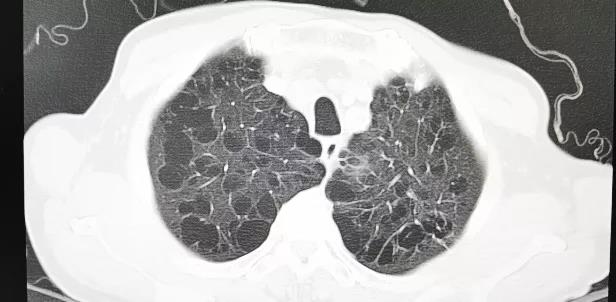

患者男性,67岁,头晕伴胸闷、胸痛6月余,术前心脏超声提示主动脉瓣增厚钙化伴重度狭窄,峰值流速4.9m/s,峰值压差94mmHg,平均跨瓣压差59mmHg,瓣口面积0.6cm2。CT显示主动脉瓣为Type I型二叶瓣,瓣叶边缘及左右冠瓣融合嵴严重钙化,致瓣口极度细窄。瓣环面积528.8mm2,测算直径25.9mm,左冠脉开口高度14.4mm,右冠脉开口高度17.5mm。患者合并重度肺气肿、多发肺大泡、支气管扩张,肺功能极差,静息状态下氧饱和度仅约80%,STS评分8.6%,属于外科手术高风险患者。

瓣叶及左右冠瓣融合嵴重度钙化 重度肺气肿、多发肺大泡